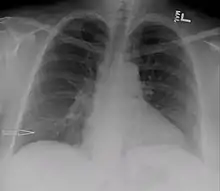

O urinotórax é definido como o encontro de urina na cavidade pleural que circunda os pulmões. Geralmente é causada por uropatia obstrutiva. É diagnosticado principalmente pela análise do líquido pleural. O tratamento envolve o tratamento da condição subjacente, que normalmente resulta na resolução do urinotórax. É uma causa extremamente rara de derrame pleural.

O urinotórax é causado pelo encontro de urina na cavidade pleural que circunda os pulmões.[1] As características das pessoas afetadas pelo urinotórax são mal definidas. Sintomas urológicos tendem a ocorrer, enquanto sintomas respiratórios são geralmente inexistentes ou leves.[2] Dificuldade respiratória, ocorrendo em moderados a grandes derrames pleurais, é o sintoma respiratório mais comum.[3] Outros sintomas incluem febre, dor abdominal, dor torácica e urinação reduzida.[2] Geralmente ocorre poucas horas após a condição causadora.[4]

Como os principais sintomas são geralmente urológicos em vez de respiratórios, a condição requer a exclusão de outras condições e a identificação de sintomas específicos antes do diagnóstico.[7] A análise do fluido pleural é uma forma de diagnosticar a condição. O líquido pleural é geralmente cor de palha e tem um cheiro distinto, como amônia. O fluido geralmente tem uma quantidade de células nucleadas de 50 a 1500 por cm3.[3] O pH do fluido é geralmente entre 5 e 7.[9] Os fatores primários para o diagnóstico de urinotórax pelo líquido pleural incluem baixo teor de proteína e alto teor de lactato desidrogenase.[10] Níveis baixos de glicose e acidez também são descritos, mas não são formas confiáveis de diagnosticar ou descartar o urinotórax.[6] O fator de diagnóstico químico mais importante do fluido é que a proporção de creatinina para soro é superior a 1 e geralmente superior a 10.[10]